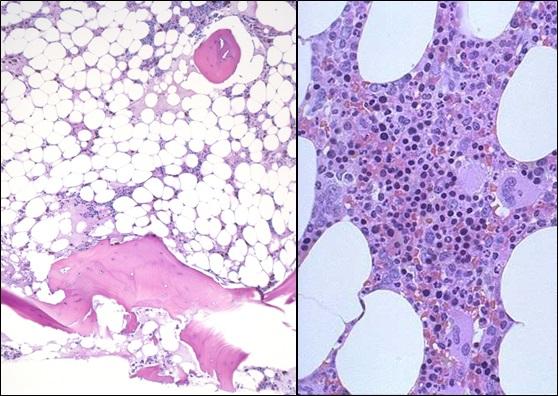

Diagnosed in about one in 250,000 people each year, aplastic anemia occurs when one's own immune system damages blood-making bone marrow cells, which gradually stop producing red and white blood cells and platelets.

Patients must receive frequent blood transfusions, take multiple medicines to suppress the autoimmune response that damages the marrow, take other drugs to prevent infections, and limit contact with the outside world to avoid infection and even minor injury. Over the long term, most patients eventually die of infections.